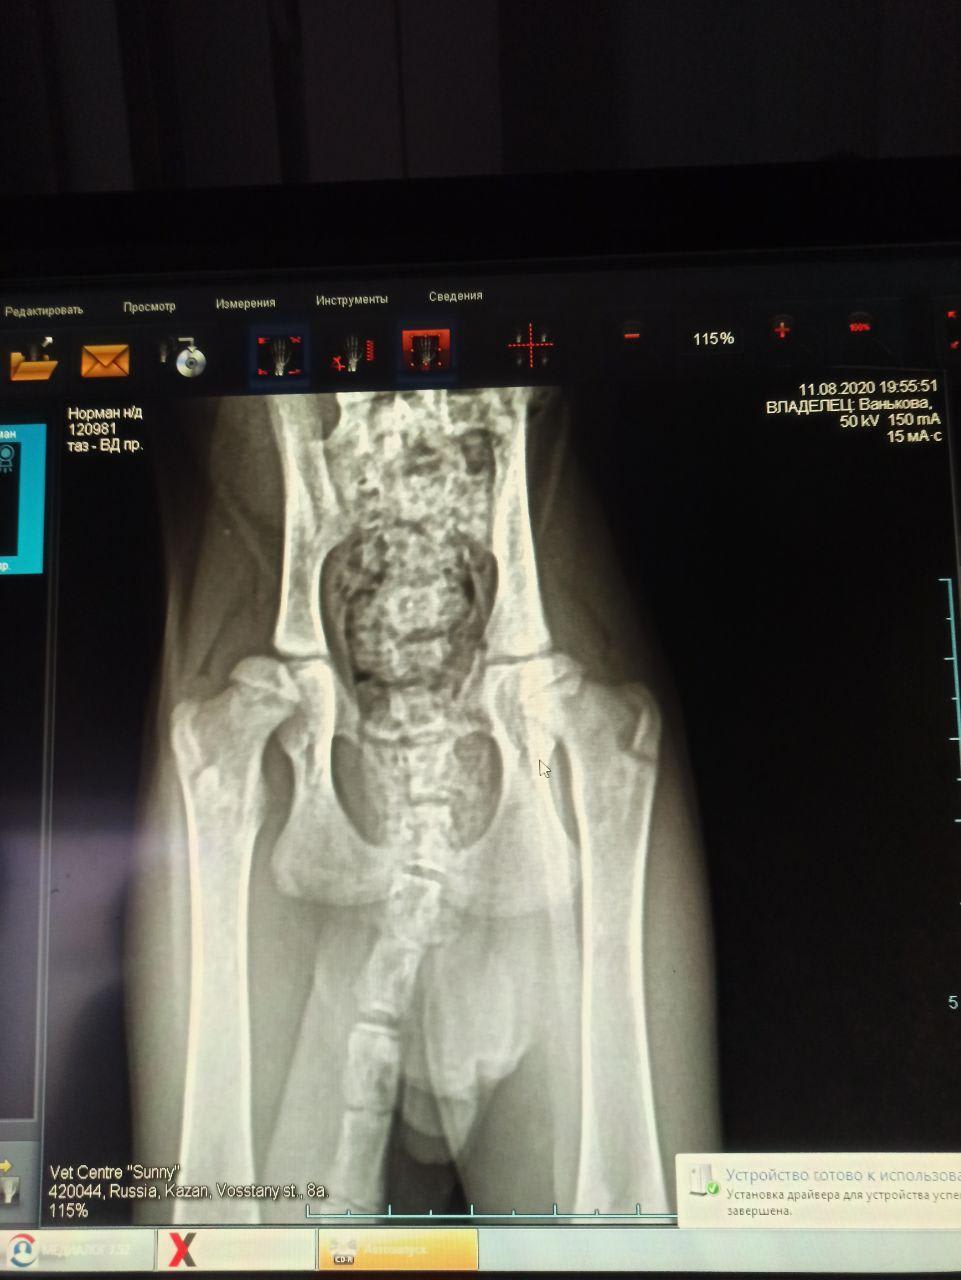

Hello. We've taken a three month age maine coon kitten and we suspect that he is suffering from hip joint dysplasia. We have got an x-ray and it looks scary, but we are not quite sure if this is an appropriate diagnostic method for kittens: maybe joints are naturally flexible at 3 months. Could you please clarify this, and say how severe is it? Thank you in advance!

Hello and thank you for contacting Petco Pet Education Center, formerly Petcoach. The hips are not fully grown or developed at this age however the subluxation that is seen in both hips is definitely abnormal and is likely to cause problems with walking and jumping. I am afraid the dysplasia looks serious and Normal may need surgery in the future to maintain normal mobility.